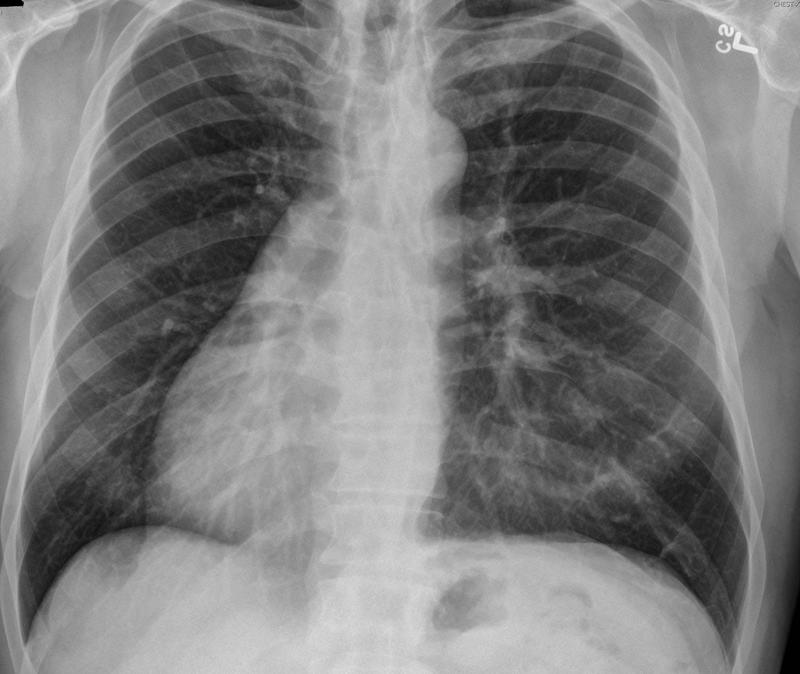

Gallery Congenital Situs inversus

Situs inversus